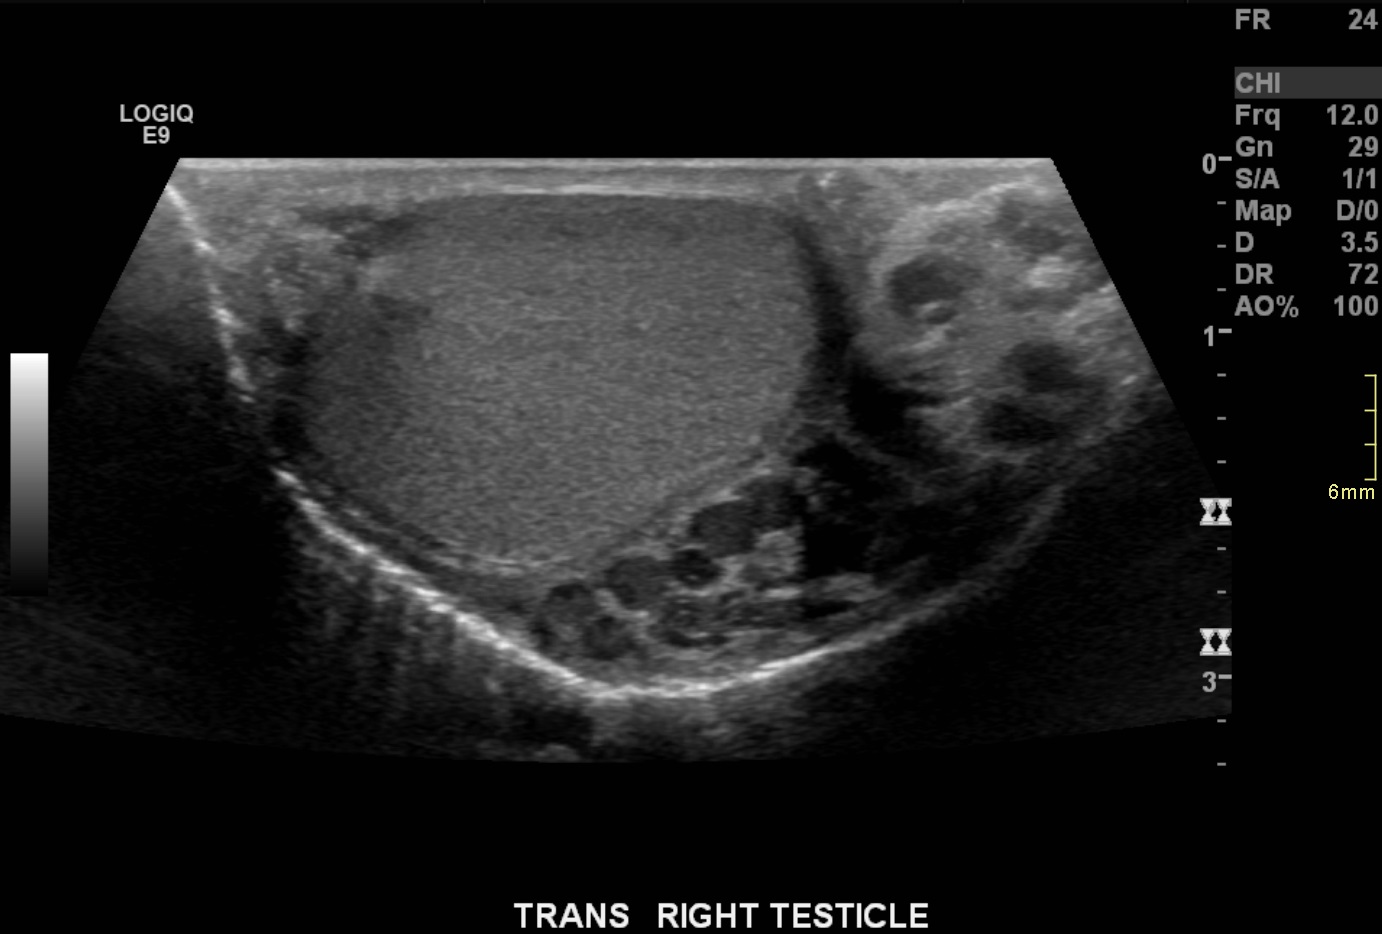

17-year-old male with a long history of left-sided varicoceles status post surgical ligation in 2015 presents with recurrence of symptoms, referred to us for left gonadal vein embolization.

Ultrasound demonstrates enlarged veins (>3 mm) adjacent to the testicle. Angiogram demonstrates reflux of contrast into the left gonadal vein to the level of the scrotum, indicating venous valvular incompetence. Coil embolization and sotradecol sclerotherapy of the left gonadal vein were performed, with an Amplatzer plug at the top of the vein. Repeat angiogram demonstrates no contrast opacification of the vein. Red arrows indicate the left gonadal vein and the blue arrows indicate the left renal vein.